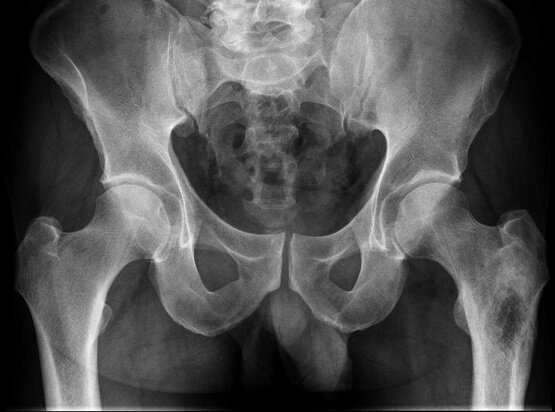

Рентгенография костей таза, что это?

Это стандартный 2-х мерный рентгеновский снимок. Обычно снимок делают в одной прямой проекции, при этом пациент располагается лежа на спине. Но в некоторых случаях, на усмотрение врача, возможны дополнительные проекции.

Что можно увидеть на исследовании?

Данный снимок позволяет оценить:

• состояние костей таза

• суставов

• костей, находящихся в основании позвоночника

• копчика

• седалищных бугров

• лонного и подвздошно-крестцового сочленения

• артрит, артроз тазобедренных суставов

• патологию тазового кольца(необходимо при планировании беременности)

• новообразования и метастазы

а так же выявить травмы, патологические изменения, аномалии развития.